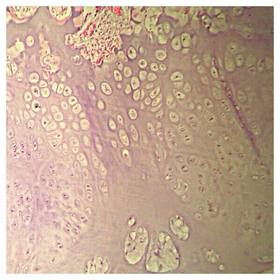

Láminas de Histología

Description

Laboratorio de histología, Bibliografía Ross Pawlina 5ta Edición.